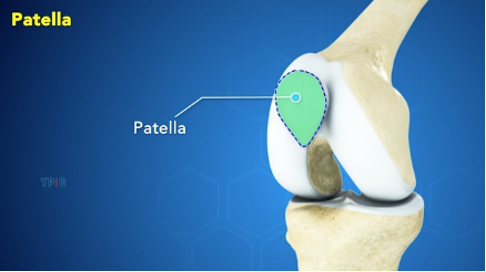

Térdkalács (patella):

A térdkalács a combfeszítő izom (quadriceps) ínába beágyazva helyezkedik el és a térdkalács ínszalaggal tapad alul a sípcsonthoz.